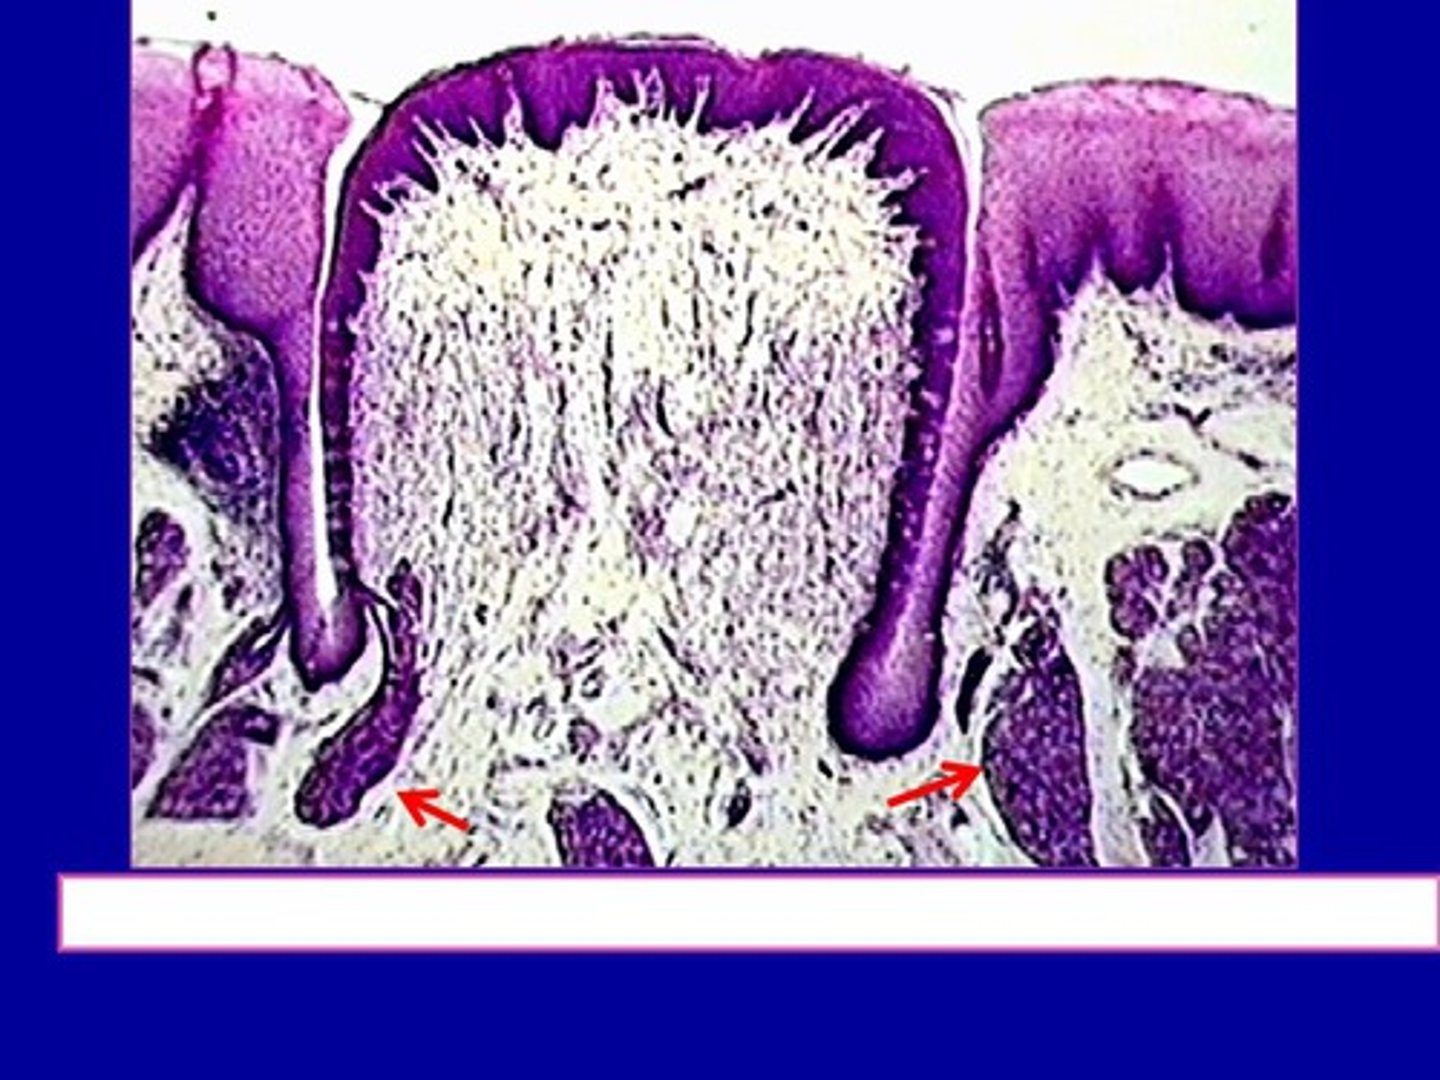

Beskriv Papilla vallatae

- Specialiserad mucosa som finns på tungan och bidrar till smaksinnet

- Smaklökarna sitter på papillans sida i vallgravarna

- Sidorna är inte keratiniserade men toppen är det

Vad finns vid papilla vallate, funktion?

von Ebners salivkörtlar som tömmer sig i vallgravarna i syfta att spola rent så att vi ska kunna känna ny smak på bästa sätt - viktigt för smakupplevelsen